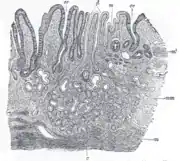

This is illustrated graphically here:

The GI tract is essentially a hollow tube connecting the mouth to the anus. The GI tract has a similar layout through out its length:

- An inner mucosal layer with an epithelial lining

- A submucosal layer

- A thin layer of muscle , the Muscularis Mucosa is at the junction of the mucosal and sub mucosal layers, outside this are the nerves of the mucosal plexus

- A muscular layer with an inner circular muscle layer and an outer longitudinal layer

- Between the muscles are the nerves of the myenteric plexus

- A serosal layer which is continuous with the mesentry